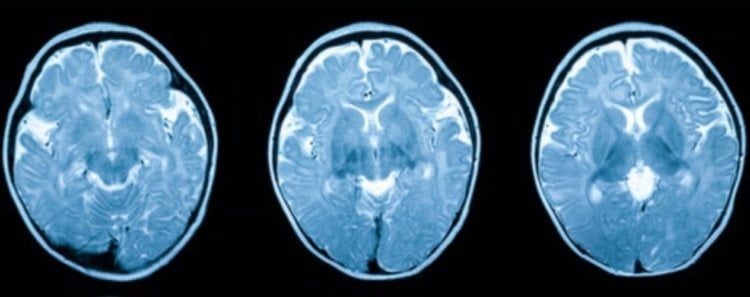

Анализ показал, что у людей 70-х годов объем головного мозга в среднем на 6,6% больше, чем у представителей 30-х годов. В частности, у них обнаружился больший объем белого и серого вещества. Белое вещество в головном мозге человека играет роль «проводника» информации между разными отделами. Серое вещество в мозге человека отвечает за обработку информации и контроль над нашими движениями. Также ученые обратили внимание на то, что за прошедшее между 1930 и 1970 годом время у людей на 5,7% увеличился объем гиппокампа. Так называется небольшая часть мозга, которая играет ключевую роль в памяти и обучении.

У людей 1930-х годов объем серого вещества в мозге был меньше, чем у современных людей. Изображение: Science Alert

О том, что головной мозг людей за последнее столетие заметно увеличился, было рассказано в научном журнале Science Alert. Это было выяснено в рамках научного исследования, в ходе которого ученые изучили параметры мозга у 3000 людей. Они учитывали данные мужчин и женщин, которые родились в 1970-е и 1930-е годы, то есть с большой разницей в возрасте.Анализ показал, что у людей 70-х годов объем головного мозга в среднем на 6,6% больше, чем у представителей 30-х годов. В частности, у них обнаружился больший объем белого и серого вещества. Белое вещество в головном мозге человека играет роль «проводника» информации между разными отделами. Серое вещество в мозге человека отвечает за обработку информации и контроль над нашими движениями. Также ученые обратили внимание на то, что за прошедшее между 1930 и 1970 годом время у людей на 5,7% увеличился объем гиппокампа. Так называется небольшая часть мозга, которая играет ключевую роль в памяти и обучении.